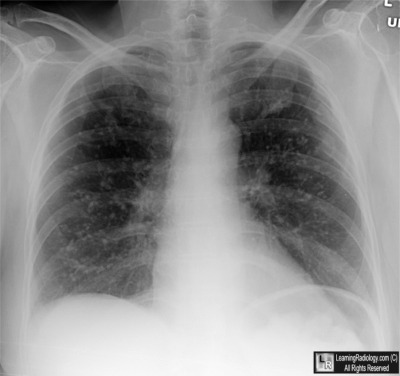

Case of the Week 556

What is the most likely diagnosis?

• 38 year-old with recent history of rash and cough

Frontal radiograph of chest

2. Varicella Pneumonia

Varicella Pneumonia

• Caused by Varicella-zoster virus (VZV)

• Spread via the respiratory route or direct contact with skin lesions, the VZV is highly contagious

• Primary infection produces chickenpox; reactivation results in zoster (shingles)

• Varicella pneumonia complicates about 2-10% of cases of VZV infection in adults

• It rarely occurs in those under age 19